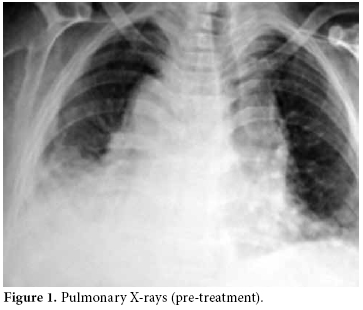

A chest radiograph showed an increased cardiothoracic index and medium to severe bilateral pleural effusion which was more pronounced in the posteroanterior right lung (figure 1).

Pulmonary X-rays showed moderate and severe bilateral pleural effusion, more pronounced in the right lung, and an increased cardiothoracic index.